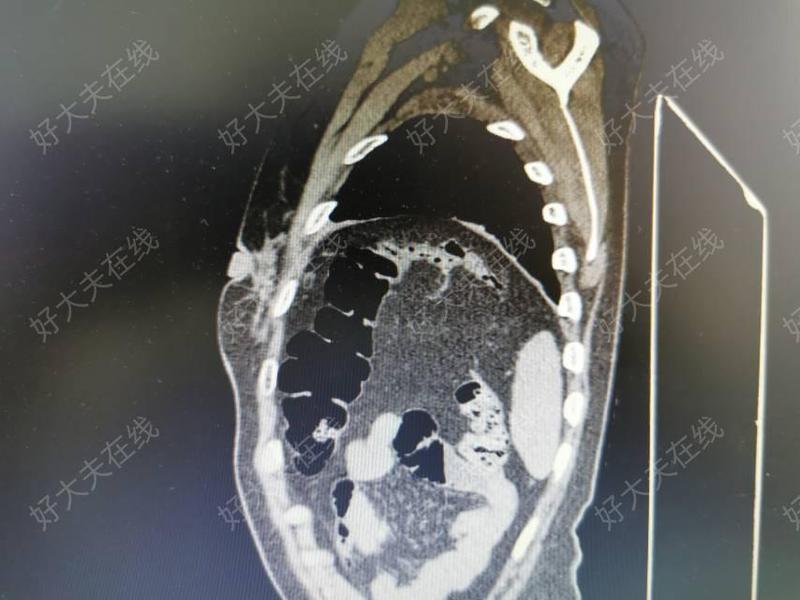

膈肌腫瘤屬于少見(jiàn)疾病,包括良性腫瘤和惡性腫瘤。良、惡性膈肌腫瘤發(fā)病率大致相等,膈肌良性腫瘤包括囊腫、纖維瘤、脂肪瘤,其中以脂肪瘤最常見(jiàn)。膈肌最常見(jiàn)的惡性腫瘤為肉瘤。除原發(fā)腫瘤外,繼發(fā)性膈肌腫瘤并不少見(jiàn)。來(lái)自胸內(nèi)和腹內(nèi)惡性病變均可直接侵及膈肌,任何侵犯或轉(zhuǎn)移到胸膜、腹膜的病變也可累及膈肌。主要惡性腫瘤包括間皮瘤、肺癌、侵襲性胸腺瘤、肝癌、食管癌和卵巢癌。良性病變?nèi)缱訉m內(nèi)膜異位癥偶也可累及膈肌。 據(jù)統(tǒng)計(jì),膈肌腫瘤發(fā)病男女比例為1.1:1。良、惡性腫瘤比例為3:2。良性腫瘤依次是囊腫(支氣管來(lái)源、間質(zhì)來(lái)源占17.7%)、脂肪瘤(11.2%)、神經(jīng)鞘瘤(5.6%)。惡性腫瘤依次為纖維肉瘤(9.3%)、平滑肌肉瘤和其他肉瘤(各4.7%)。左、右側(cè)膈肌腫瘤發(fā)生率大致相等。 良性腫瘤多無(wú)癥狀,在查體X線檢查時(shí)偶然發(fā)現(xiàn)。惡性腫瘤常有胸痛,腫瘤較大擠壓肺臟可引起呼吸困難,侵犯膈神經(jīng)時(shí)疼痛可放射至肩部和上腹部,腫瘤侵犯肺組織可有咳嗽、咯血或氣短。腫瘤向腹腔生長(zhǎng)可產(chǎn)生胃腸道癥狀和肝區(qū)疼痛。也有近1/3患者無(wú)癥狀。 由于橫膈區(qū)解剖較為復(fù)雜,膈肌病變術(shù)前往往診斷不清。它容易與肺、縱隔特別是肝臟病變相混淆。膈肌腫瘤常以發(fā)生點(diǎn)為中心,向各個(gè)方向發(fā)展,累及周圍的組織、器官,有時(shí)很難與膈上、膈下、肺臟基底段、心臟、縱隔等處的腫瘤鑒別開(kāi)來(lái)。 X線檢查發(fā)現(xiàn)膈肌上有邊緣光滑的球形或塊狀陰影,惡性者呈分葉狀,隨膈肌上下活動(dòng),肺、肝或脾受腫瘤擠壓而移位。惡性腫瘤侵犯膈神經(jīng),引起膈麻痹,橫膈升高且無(wú)運(yùn)動(dòng),常伴有胸腔積液或腹水。CT是目前診斷膈肌腫瘤的主要方法,大部分病例經(jīng)CT檢查可以確診,但是當(dāng)腫瘤巨大致周圍結(jié)構(gòu)不清,CT亦難以確切診斷。 (女性患者,33歲,自感左季肋部不適2年,發(fā)現(xiàn)左前胸壁腫物1個(gè)月入院,圖一CT顯示左前下胸腔內(nèi)腫物,大小18cm×15cm×12cm,橢圓形,與肌和前胸壁分界不清,行左后側(cè)切口開(kāi)胸,手術(shù)發(fā)現(xiàn)腫瘤來(lái)源于膈肌胸骨部和肋部,侵及膈肌、心包和部分肋骨。完整切除腫瘤、部分心包和肋骨,滌綸片修補(bǔ)膈肌、心包和胸壁缺損。術(shù)后病理診斷“膈肌纖維瘤”) (圖二為矢狀位CT像顯示左膈肌腫瘤) 一旦明確膈肌腫瘤,均應(yīng)采取手術(shù)治療。一般說(shuō)來(lái),大多數(shù)腫瘤較小,切除和重建膈肌并不困難。偶爾在擴(kuò)大切除或縫合有張力時(shí),需要補(bǔ)片替代膈肌缺損。切除后重建一般用不可吸收材料修補(bǔ)。修補(bǔ)左側(cè)膈肌缺損時(shí)應(yīng)避免腹腔臟器疝入胸腔,右側(cè)由于肝臟保護(hù),疝入的機(jī)會(huì)較少。良性腫瘤和囊腫切除后,效果良好,隨診多年無(wú)復(fù)發(fā)。膈肌惡性腫瘤切除后常常需要進(jìn)行放療或化療,以預(yù)防腫瘤復(fù)發(fā)或轉(zhuǎn)移。

張臨友醫(yī)生的科普號(hào)2020年07月21日9382